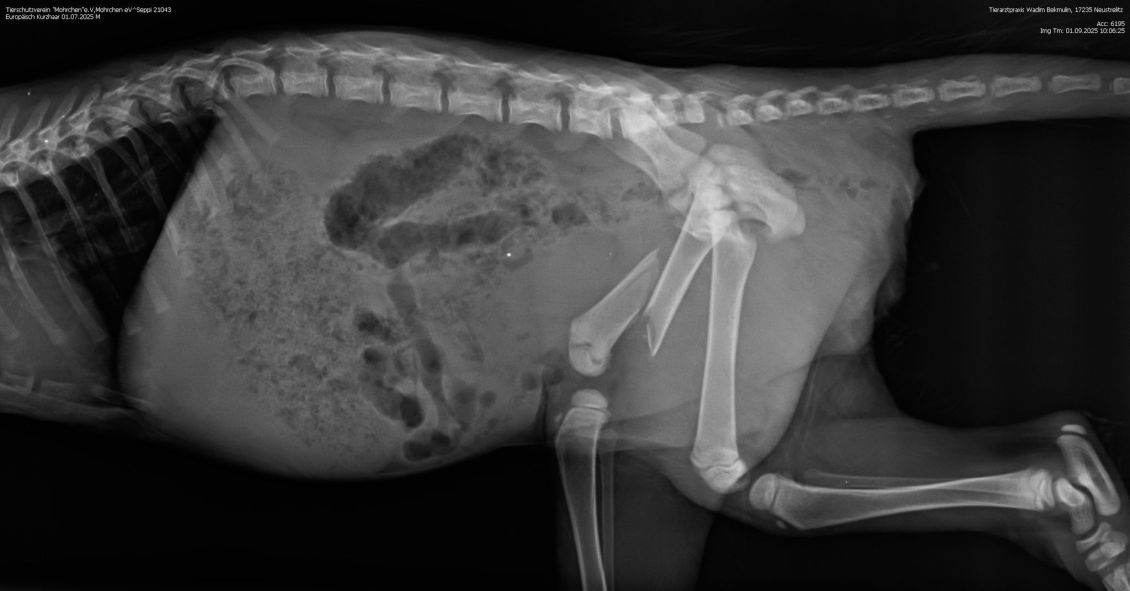

Ganz ohne Operation wird es aber dennoch nicht gehen: Auf dem Röntgenbild wurde festgestellt, dass Seppi einen Schwanzabriss erlitten hat. Sein Schwanz muss daher amputiert werden. Daran führt leider kein Weg vorbei.

Nun kann es schnell gehen - und das ist auch nötig: Denn die Röntgenbilder zeigen,dass der Oberschenkel stark verschoben ist und ihm große Schmerzen bereitet.

Beim Tierarzt haben wir erfahren, dass Seppi einen schweren Oberschenkelbruch erlitten hat. Damit er schmerzfrei laufen kann und keine bleibenden Schäden entstehen,

muss der kleine Kerl dringend operiert werden. Die Kosten werden sich voraussichtlich auf ca. 1.300 Euro belaufen. Eine Summe, die wir nicht alleine stemmen können. Deshalb bitten wir um Hilfe. Jede Spende, egal in welcher Höhe, zählt. Unser Ziel ist es, dass Seppi eine gute Chance auf eine gesundes Leben erhält.